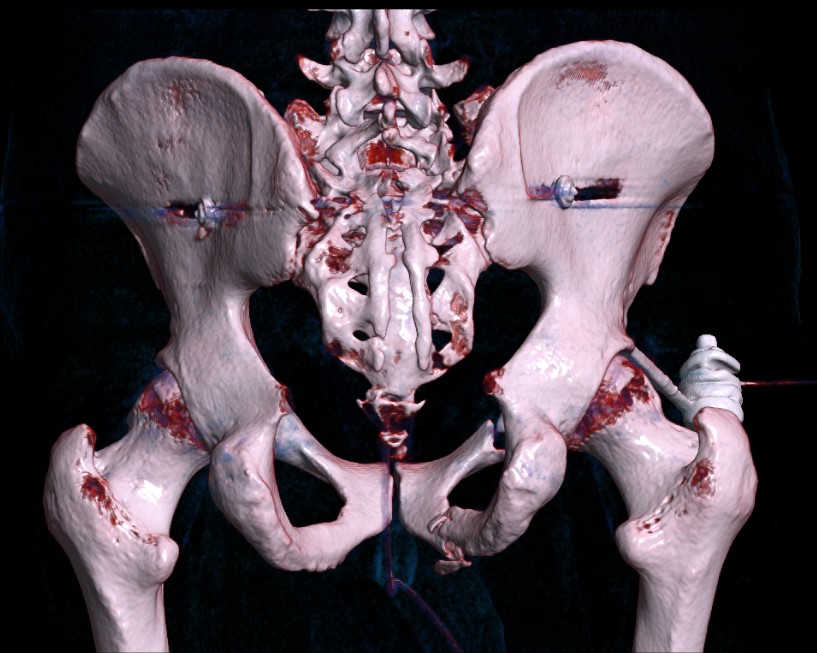

Operative management

Indications

> 10 mm displacement

EUA / lateral stress view

- complete sacral fracture with instability

Technique

Posterior fixation

Anterior fixation if unstable or bilateral pubic rami fractures

Results posterior +/- anterior fixation

Percutaneous sacroiliac screws

Anterior fixation

- instability following posterior fixation

- bilateral pubic rami fractures

Options

- plate - modified stoppa

- percutaneous ramus screws

- external fixation

LC-1 with anterior external fixation Plating of bilateral pubic rami fractures